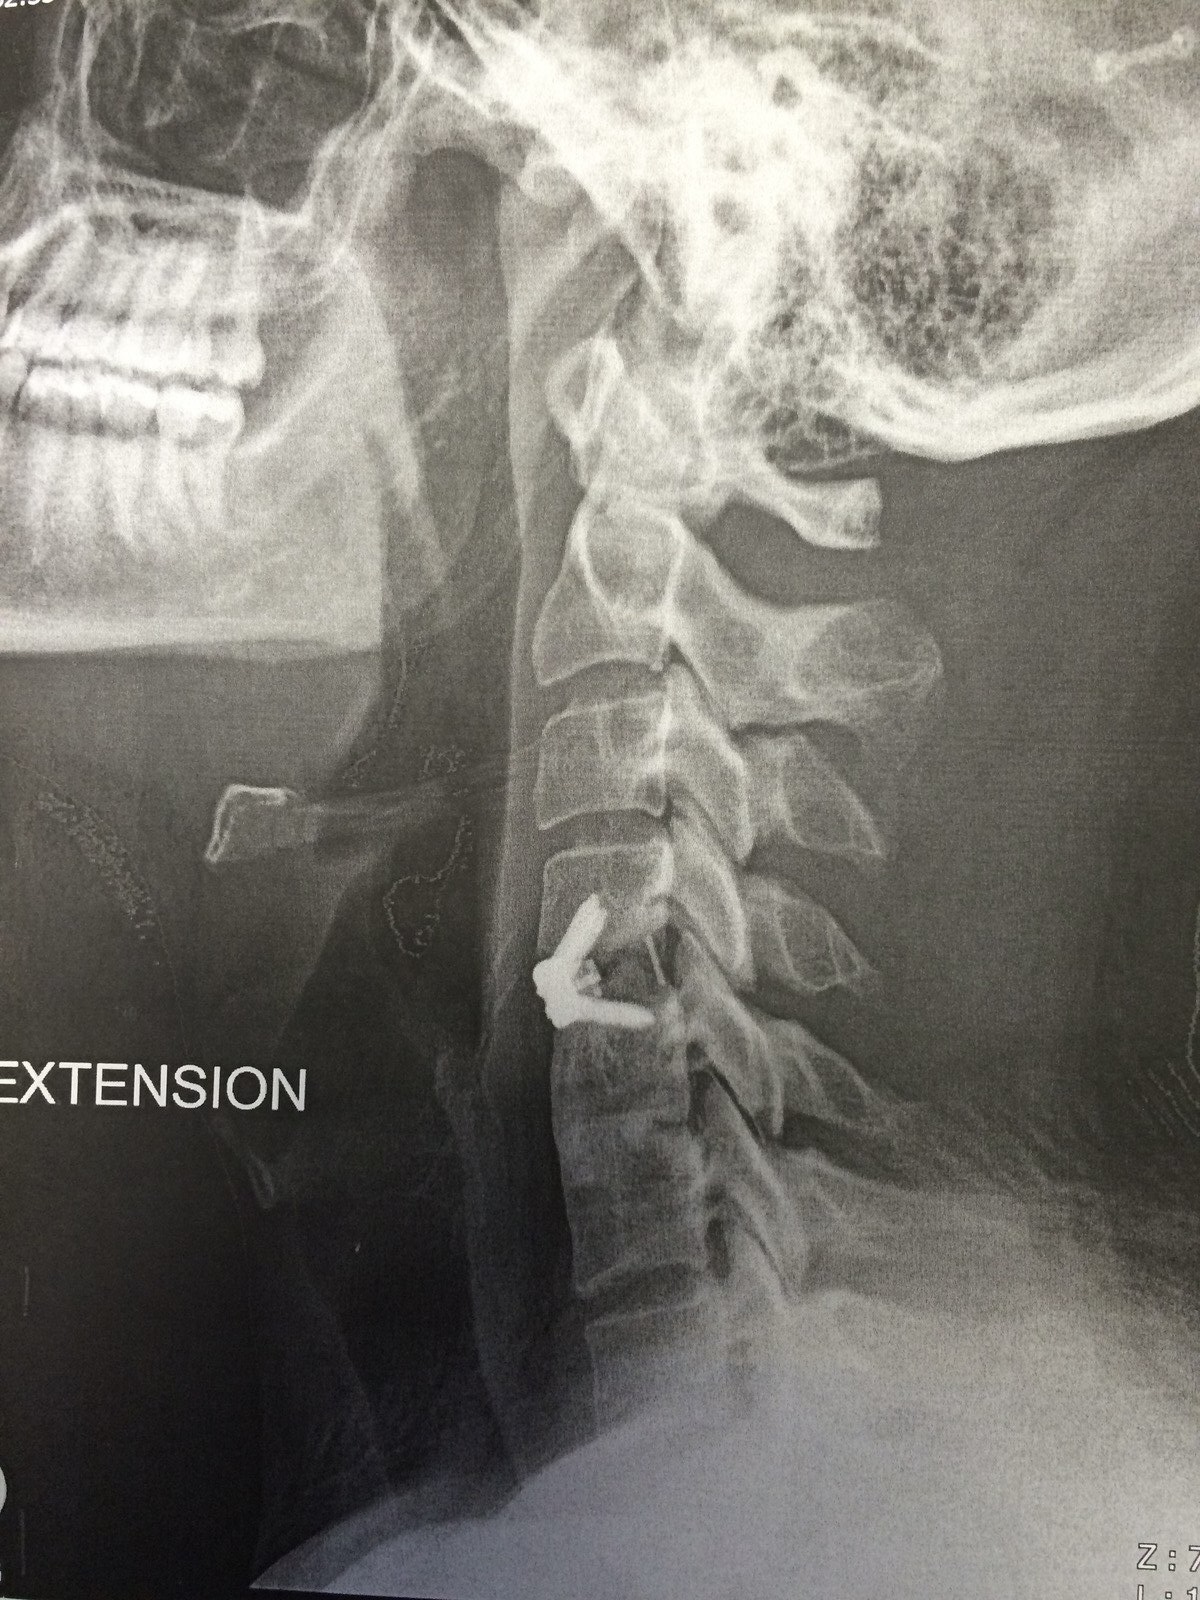

의료 팀은 영상 진단을 통해 얻은 정보를 바탕으로 수술 계획을 세웁니다. 손상된 디스크의 위치, 척추의 구조적 문제, 신경 압박의 정도 등을 고려하여 수술 접근 방법과 필요한 기구를 결정합니다.

수술은 주로 목의 앞쪽(전방 접근법) 또는 뒤쪽(후방 접근법)을 통해 이루어집니다.

전방 접근법은 대부분의 경우에 사용되며, 손상된 디스크와 신경에 보다 쉽게 접근할 수 있게 해줍니다.

뼈 유합

디스크 제거 후, 의료 팀은 뼈 이식재나 인공 디스크를 사용하여 척추의 두 뼈를 함께 유합시킵니다.

이는 척추의 안정성을 회복하고, 추가적인 손상을 방지하기 위해 수행됩니다.